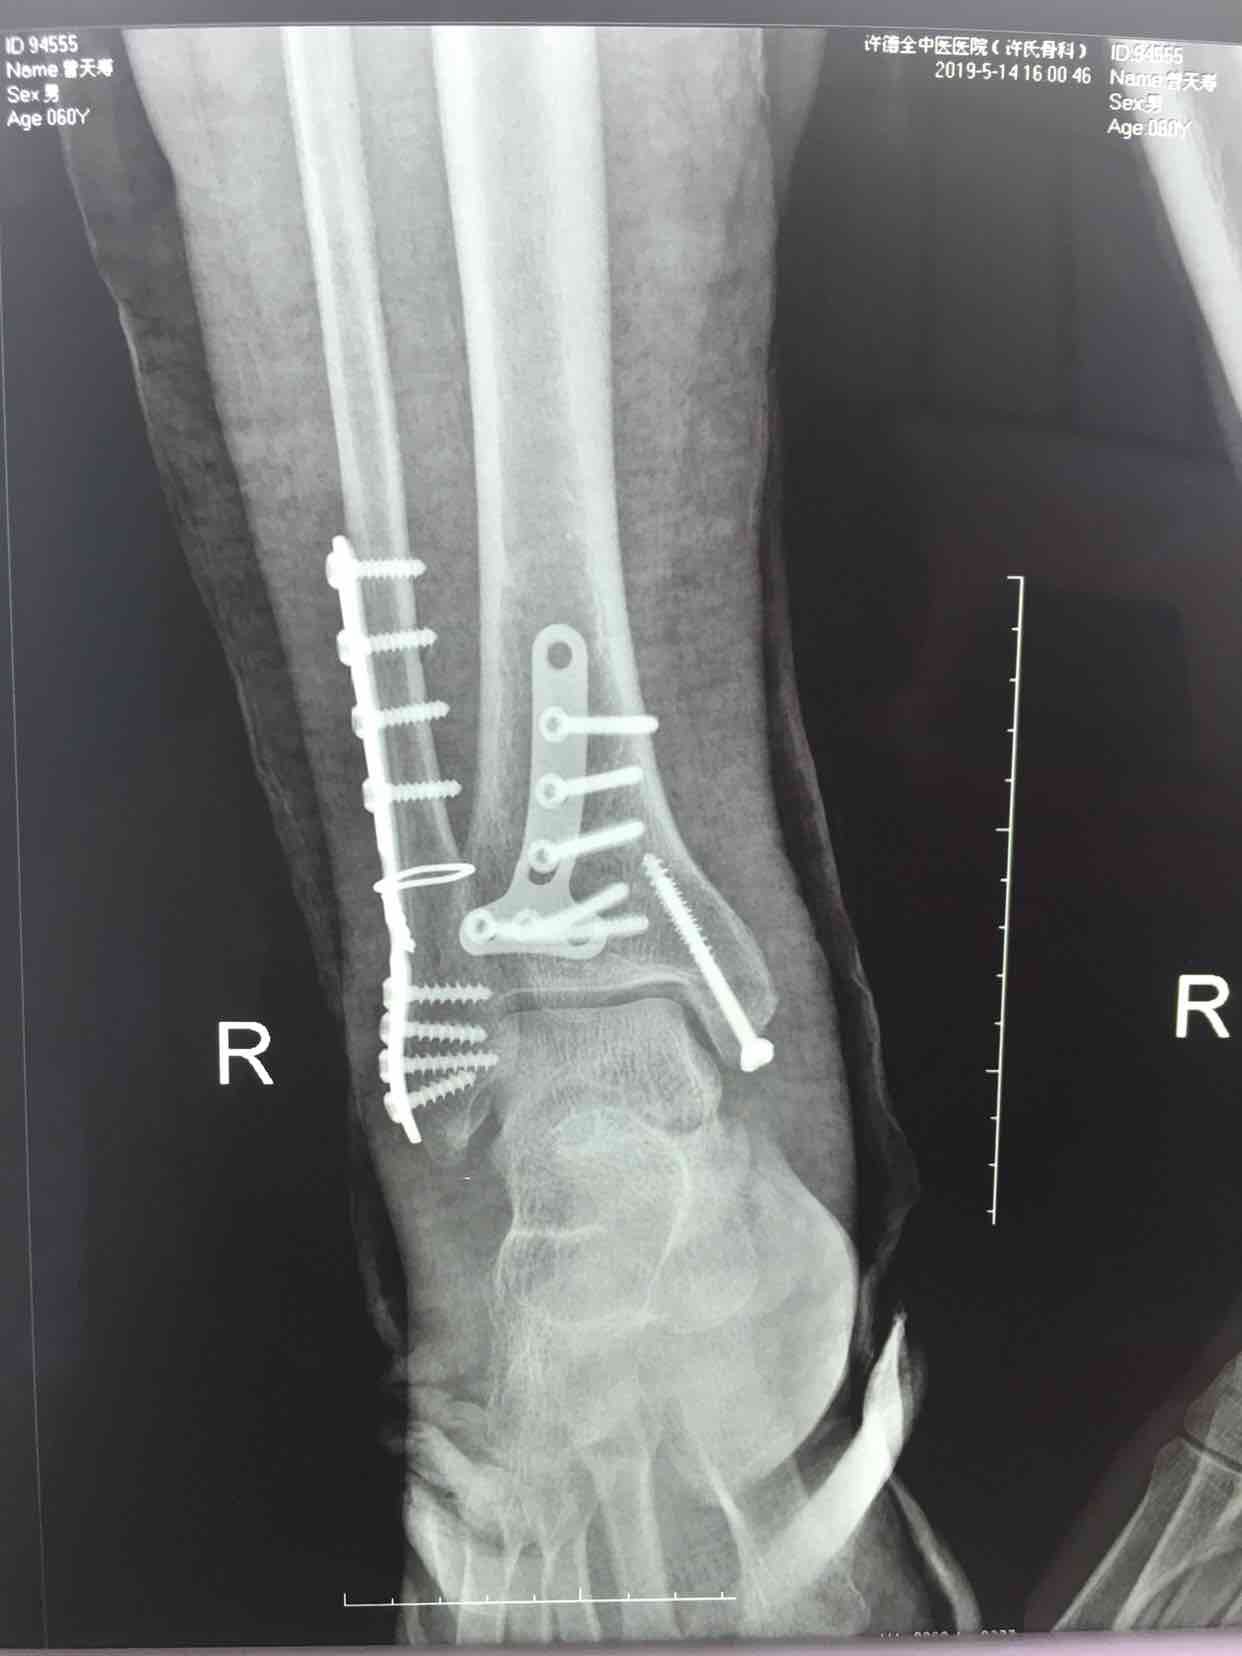

三踝骨折并胫距关节脱位(切复内固定术)

摔伤后右踝肿痛,畸形,活动受限1小时入院。既往身体健康,无特殊不良嗜好。

生命体征平稳,心肺复未见异常。右踝部肿胀,局部皮色发红,皮温高,畸形,压痛及纵叩痛阳性,可及骨擦音或骨擦感,踝关节活动受限,末梢血运感觉正常。

诊断三踝骨折并胫距关节脱位完善术前检查,待肿胀消退后在腰麻下行切复内固定术,术后石膏托固定,抗炎,消肿等处理。